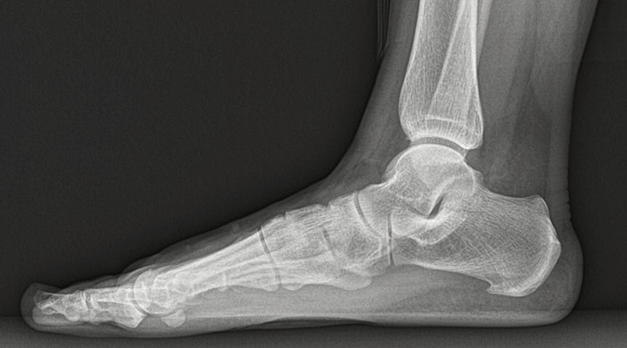

우리의 발바닥에는 근육이 있는데 그중 족저근막은 발뒤꿈치에서 시작해서 발바닥 앞쪽 5개 분지로 이어져 발가락 기저부에 부착되어 있는 강인하고 두꺼운 섬유띠를 말합니다.

족저근막은 발을 들어 올리는데 도움을 주는데 족저근막염은 바로 이 족저근막에 생기는 염증으로 발에 스트레스가 증가하거나 단기간 몸무게가 증가한다면 발병하기 쉬워지며 발의 모양상 오목발이나 평발이어도 발병률은 높아질 수 있습니다.